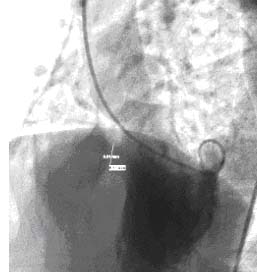

室間隔肌部2.1封堵前後左心室造影結果如圖:封堵前左心室造影

1.2方法患者經1%利多卡因局部麻醉,分別行右股動脈,右股靜脈穿刺,經動脈鞘管插入6F豬尾導管至左心室,取左前斜52°加頭25°行左心室造影,證實室間隔肌部缺損,距主動脈瓣約6mm;缺損口左室面寬ф12mm,右室面最窄徑ф10mm,管徑長約7mm,分流量大;造影后經改良豬尾導管建立右股動脈—左心室—室缺口—右心室—右股靜脈軌道,沿軌道經股靜脈送9F長鞘管送至主動脈瓣上,通過豬尾導管和導引鋼絲調試,將長鞘管送入左心室並指向心尖。選擇ф12mm長7mm國產(先健科技)肌部封堵器,經操縱桿在X線透視下推送至左心室,先打開左心室碟片,輕輕回拉,使其與室間隔左室面貼緊,利用手感使封堵卡入缺損處,回拉稍有阻力,退輸送鞘管,使右心室面碟片打開。聽診心臟雜音消失;經胸彩色都卜勒超聲心動圖及左心室造影均證實:封堵器位置固定良好,無殘餘分流,對三尖瓣及主動脈瓣等周邊組織無影響,逆時針鏇轉操縱桿釋放封堵器。